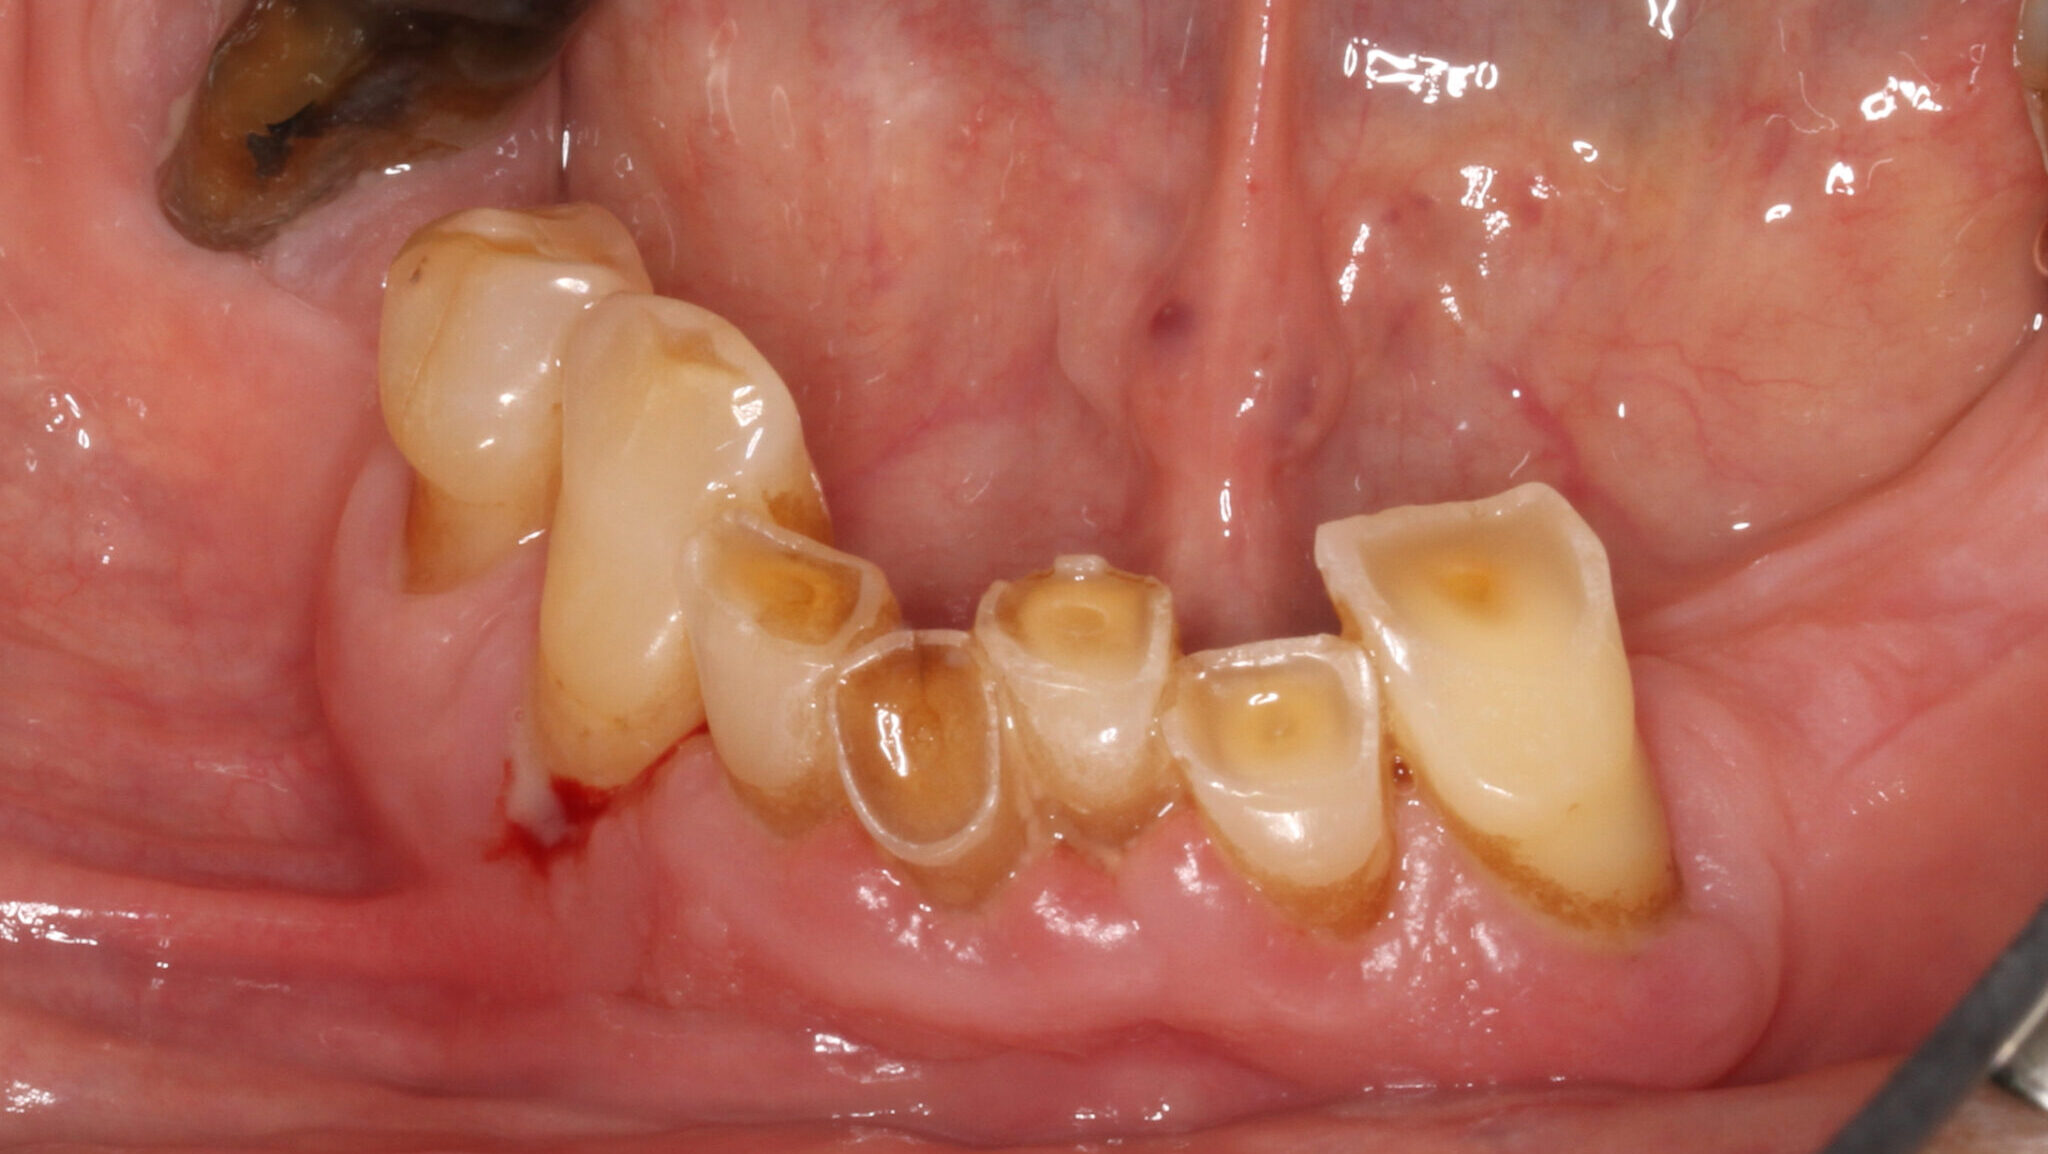

Prosthodontic Treatment of The Severely Worn Dentition

Introduction The severely worn dentition often poses a challenge to the restorative clinician. Diagnosis and treatment planning involve multidisciplinary and in-depth evaluation of etiological, esthetic, occlusal, functional and preventive factors. Modern dentistry has made tremendous progress in areas of decay prevention, treatment of periodontitis and preservation of the natural dentition. Patients in general are more … Read more